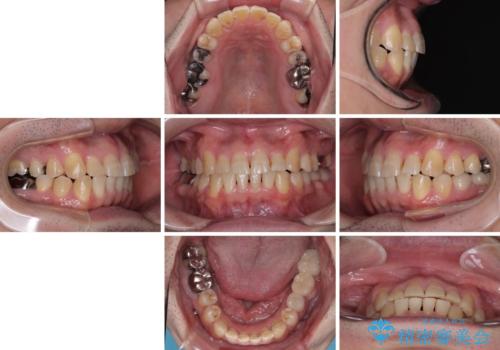

- 近医にてブリッジ治療を行った歯が痛くてたまらないとのことで来院された患者様です。

診察を行ったところ、奥の土台になっている歯は神経組織が失活しており、根尖部に病変があり、そこが原因で痛みを生じている状態でした。

根管治療を行うためにブリッジを除去したところ、むし歯が歯肉の奥深くにあまで及んでいたため、歯周外科処置によりむし歯が歯肉縁より浅い位置へと改善することとしました。

ここまでの治療を提案したところで、折角なのでしっかり治療を行いたいとのことで、前歯のデコボコやクロスバイトを改善するための矯正治療を行うこととしました。

まずは奥歯の痛みを改善し、その後矯正治療を行い、最後にオールセラミックブリッジによる補綴治療を行うこととしました。